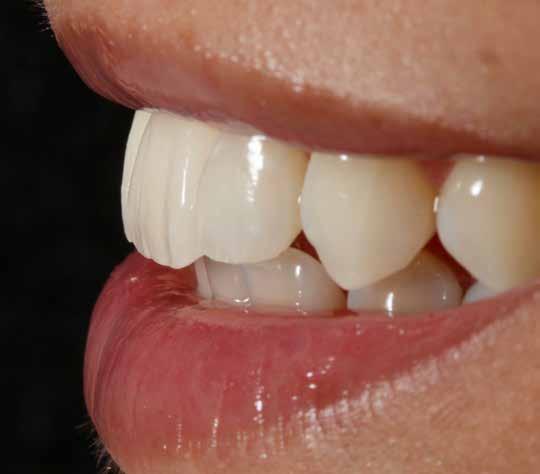

Az oxigén inhibíciós réteg kialakulásának elkerülése érdekében a kerámiafelszíneket glicerin géllel (Liquid Strip, Ivoclar Vivadent, Schaan, Liechtenstein) borítottuk, majd ezeket a felszíneket ismét 20-20 másodpercen keresztül világítottuk. A végeredmény megfelelt a páciens esztétikai igényeinek (6. a. ábra). Az átadott restaurátumok épségének megőrzése érdekében, a páciens számára éjszakai fogvédő sín készült. Az ötéves kontroll alkalmával megállapítottuk, hogy az elvégzett kezelésünk továbbra is sikeresnek tekinthető (6. b. ábra)

Az általunk alkalmazott adhezív rendszerek hatékonyságát nagymértékben növelhetjük azáltal, hogy a fogakat minimál invazív módon, azaz csak zománcon belül preparáljuk, és a kerámia héjakat kofferdám izolálásban ragasztjuk. Jelen esetismertetésünknek az volt a célja, hogy bemutassuk, hogyan lehet az adekvát módon kivitelezett kofferdám izolálással megelőzni

a munkaterület nyállal, vérrel vagy szulkusz-váladékkal történő kontaminációját. A megfelelő méretben kialakított perforációs nyílások és köztük lévő optimális távolság elengedhetetlen ahhoz, hogy a kofferdámot ideális módon tudjuk felhelyezni. Ezzel az esettel azt is bizonyítjuk, hogy a gumilepedő levegőfújással, fogselyemmel és teflonszalagok segítségével történő beforgatásával az ínyvérzés kialakulását el lehet kerülni. Ismételten szeretnénk hangsúlyozni, hogy a megfelelő kofferdám kapcsok használata nélkül nem tudtuk volna a preparált csonkszélt a gumilepedő szélétől eltartani. A kezelés során elért eredményeket jól alátámasztotta, hogy a páciens az ötéves kontroll vizsgálat során teljesen elégedett volt.

A páciens elégedett volt a végleges restaurátumok színével, formájával és méretével. A kezelés végeredménye kielégítette az esztétikai elvárásait (9. ábra). A frissen átadott restaurátumok épségének megőrzése érdekében a páciens számára éjszakai fogvédősínt készítettünk. A páciensünk a négyéves kontrollvizsgálat során is nagyon elégedett volt a kezelés eredményével. A korábban meglévő fekete háromszögek eltűnésének különösképpen örült (9. és 10. ábrák)